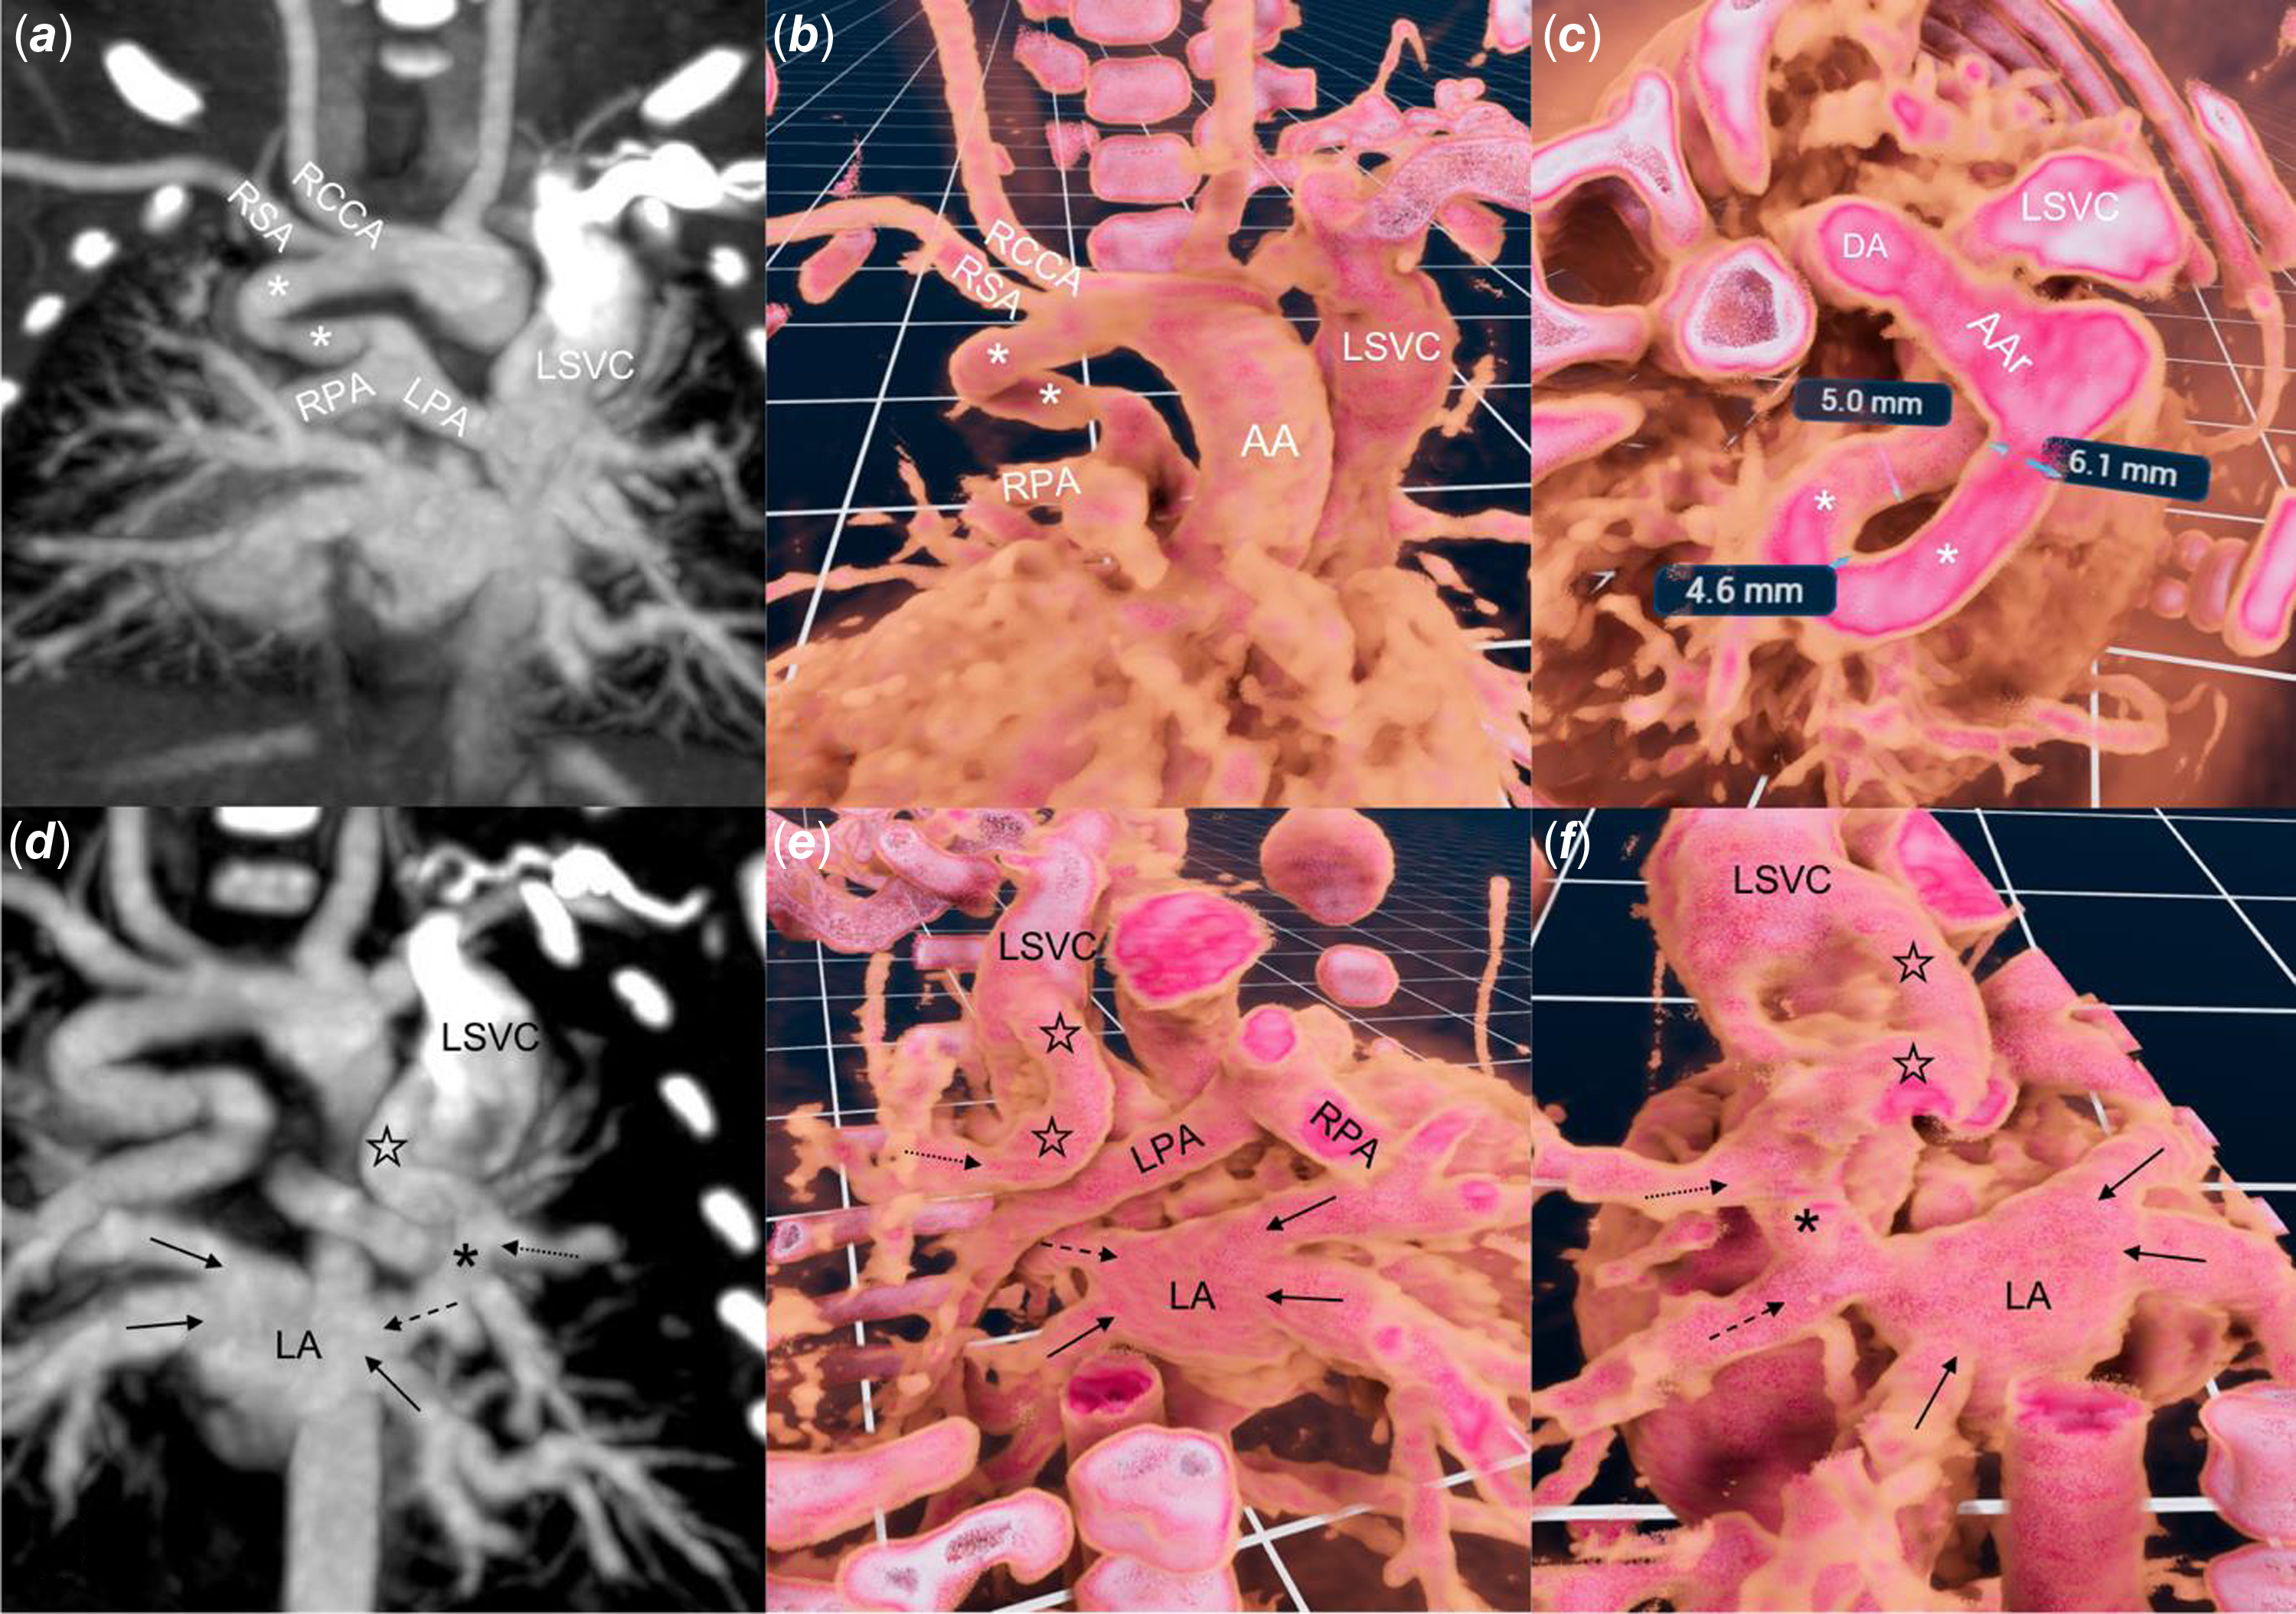

Figure 1. Standard two-dimensional ( a, d ) CT and three-dimensional ( b, c, e, f ) reconstruction with virtual reality software (VMersive, VR—Learning, Warsaw, Poland). ( a, b ) a right sided, tortuous and narrowed at the pulmonary end of ductus arteriosus (white asterix) supplies native pulmonary arteries. ( c ) wide along most of its length ductus arteriosus takes a 180° turn. ( d, e, f ) a vertical vein (black stars) joins the left superior vena cava and the left upper pulmonary vein (dotted arrow), which than, anterior to the right pulmonary artery, connects (black asterix) with the left middle pulmonary vein (dashed arrow) and together with three remaining veins (black arrows) drain to the left atrium. AA = Ascending aorta, AAr = Aortic Arch, LPA = Left Pulmonary Artery, RCCA = Right Common Carotid Artery, RSA = Right Subclavian Artery.

In view of the complex anatomy, a contrast CT was performed to plan the initial stage of palliation (Figure 1(a) and (d)). A three-dimensional dataset was analysed in virtual reality using dedicated software (VMersive, Warsaw, Poland). The imaging confirmed a left-sided aortic arch with a right-sided ductus arteriosus that narrowed at the pulmonary end (Figure 1(b) and (c); Supplementary Video 1). The left superior pulmonary vein drained into the vertical vein, which had a connection with the left superior vena cava and continued into the left atrium through the left middle pulmonary vein. (Figure 1(e) and (f); Supplementary Video 1). After a multidisciplinary discussion, we opted for percutaneous first-stage palliation, enlargement of the atrial communication, and stenting of the ductus arteriosus, to offer a less invasive approach (excluding sternotomy and cardiopulmonary bypass) suitable for a fragile newborn.